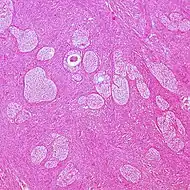

Adult granulosa cell tumor 1%Almost 100%Small, bland, cuboidal to polygonal cells in various patterns.[9]